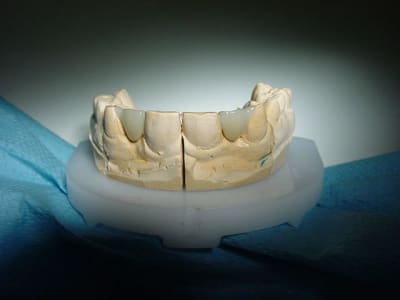

29/12/2010 à 22h41

résultat premier bridges collés Emax

à voir dans le temps...

gestion du temps provisoire pas évident

surtout sur un étudiant présent que le WE..

et encore désolé pour l'iconographie (pas ma préoccupation majeure car un peu pris ds le rythme .. )

ça a vraiment le mérite d'avoir ete tenté , bravo ! surtout sur un etudiant , patient à vie risquée (sandwich, barre cereales etc ...) donnera une bonne idee du futur .

et puis le résultat est top compte tenu de la situation spaciale des collatérales ...beaux rendu de teinte et aussi du collage des canines ...

Pourquoi ne pas avoir "travaillé" plus les embrasures, la papille va pas etre contente.

fraise tungstène spéciale c'est encore faisable, sans compromettre la solidité.

belle teinte.

bonsoir,j'ai eu interdiction de retouche par ma prothésiste sous peine de non respect des impératifs de solidité au niveau des jonctions.

donc pas de retouche des embrasures.....dommage effectivement